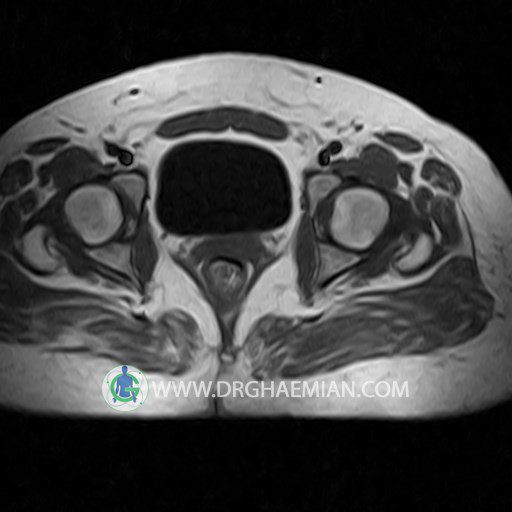

پزشکان اغلب از تصویربرداری ام آر آی برای تشخیص و درمان عارضه های پزشکی که فقط با استفاده از اشعه ایکس یا میدان مغناطیسی و امواج رادیویی قابل مشاهده است، استفاده می کنند. دستگاه ام آر آی تصاویر دقیق از ساختار های داخلی بدن ایجاد می کند. در این کیس کیست بارتولین لگن و تجمع دورمقعدی و کیست ساده ایی در تخمک چپی دیده می شود.

HIP JOINT MRI

( without contrast )

Technique : coronal STIR , coronal T2 , Axial T1 , axial T2 .

REPORT:

The femoral heads and acetabula are normal shape , signal intensity and the femoral heads are well covered by the acetabular margins .

The joint spaces are of normal width without fluid collection .

the articuler surfaces are smooth and congruent and show normal cortical thickness .

there are no marginal osteophytes or subchondral signal changes .

The bone marrow shows normal signal intensity , especially in the femoral head and neck .

Each femoral shaft has normal margins and contains a normal bone marrow signal .

– Simple cyst (28×32mm) in left ovary

– Cyst like lesion (20×25mm) in right vaginal wall suggestive for bartholin cyst and perianal collection

are seen.

COMMENT: Clinical correlation is recommended.